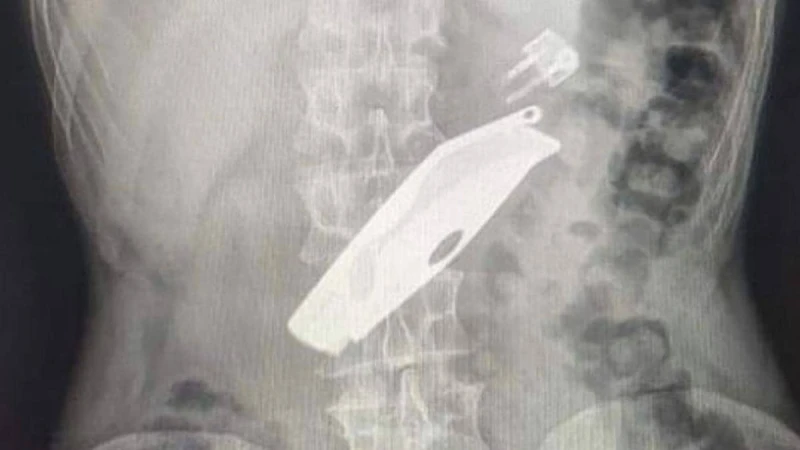

Науқас Уалихан ауданының ауруханасына түнде түсіпті. Оның тыныс алуы нашарлап, сөйлей алмапты. Рентген арқылы ақ халаттылар ер азаматтың ас қорыту жолында тұрып қалған бәкі мен от жағуға арналған шақпақты анықтаған. Бөгде заттар өкпеге ауырлық түсірген. Мамандар отаның бір сағаттан ұзақ жасалғанын айтады. Өз-өзіне келген азамат отбасылық проблемалардың салдарынан осылай жасағанын айтыпты.

"Санавиациямен келген дәрігерлермен бірігіп ауыр ота әске асырылыд. Атап айтсақ, лапаротомия, гастротомия, асқазаннан екі бөгде зат алынды. Қазір науқастың жағдайы орта, ол палатаға ауыстырылды", -  дейді хирург Дәулет Серғазин